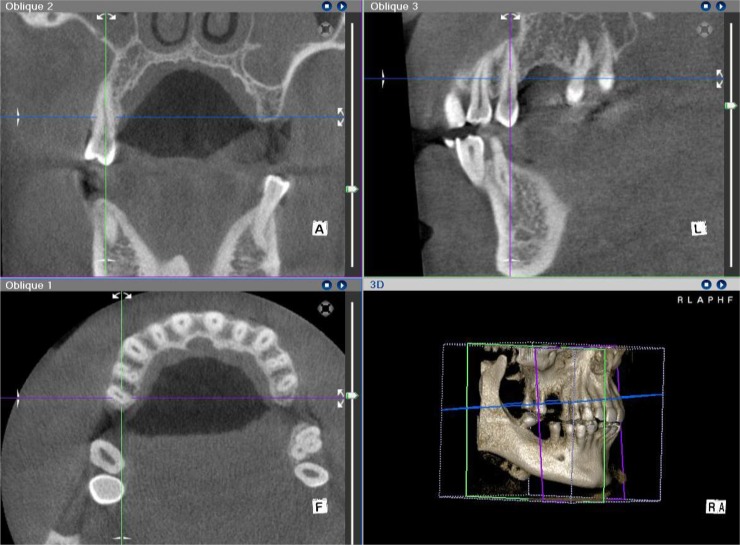

Materials and methods: A study of diagnostic test accuracy was designed and 38 teeth from candidates for dental implant treatment were selected. On CBCT scans, the amount of bone resorption in the buccal, lingual/palatal, mesial and distal surfaces was determined by measuring the distance from the cementoenamel junction to the alveolar crest (normal group: 0-1.5mm, mild bone loss: 1.6-3mm, moderate bone loss: 3.1-4.5mm and severe bone loss: >4.5mm). During the surgical phase, bone loss was measured at the same sites using a periodontal probe. The values were then compared by McNemar's test.

Results: In the buccal, lingual/palatal, mesial and distal surfaces, no significant difference was observed between the values obtained using CBCT and the surgical method. The correlation between CBCT and surgical method was mainly based on the estimation of the degree of bone resorption. CBCT was capable of showing various levels of resorption in all surfaces with high sensitivity, specificity, positive predictive value and negative predictive value compared to the surgical method.